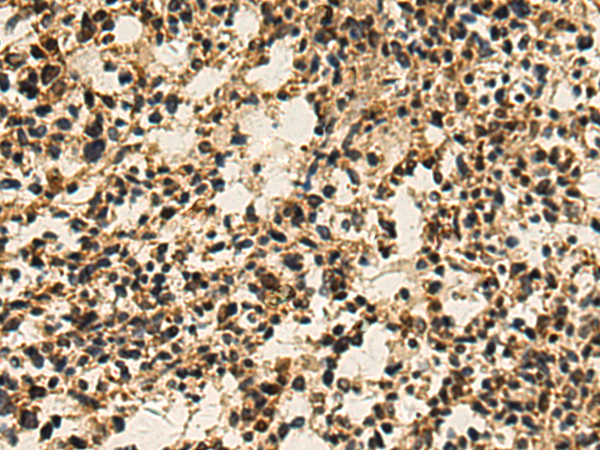

分类: 科研抗体货号: P10442别名: IF; GIF; INF; IFMH; TCN3应用: IHC反应种属: Human, Mouse, Rat